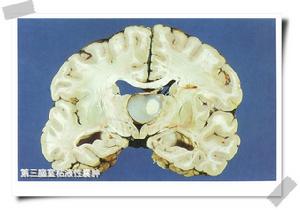

第三腦室腫瘤基本概述

第三腦室2.第三腦室腫瘤概述:原發於第三腦室內的腫瘤有膠質瘤、畸胎瘤、膽脂瘤和膠樣囊腫。其發病率約占顱內腫瘤的3%,多見於兒童及青年人,男多於女。腫瘤多較易阻塞腦脊液循環通路,因此常導致顱內壓增高,這也是病人就診的原因。突入第三腦室內生長的腫瘤,除有因阻塞腦脊液循環通路造成顱內壓增高外,還具有其原發部位腦組織受侵犯所產生的局灶症狀和體徵以及其所特有的X線徵象。